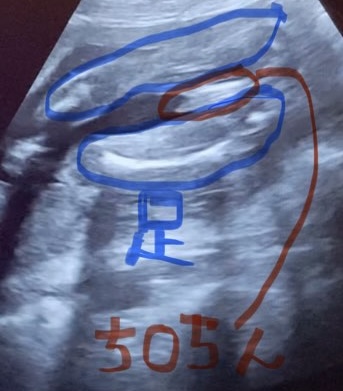

1番気になるお股の部分をスローで確認したところ「これはち◯ちん?」と思うような代物が映りました。

それからというもの毎晩毎晩、何十回、何百回も同じ動画を見返していました。ちょっと病的だったと思います。

夫やほかの人に見てもらったところ「絶対、ち◯ちんやん!」と言われましたが、うっすら気づきながらも「いやいや、これは足の親指やろ!」と男の子と判断するのを、私の脳が拒絶していました。